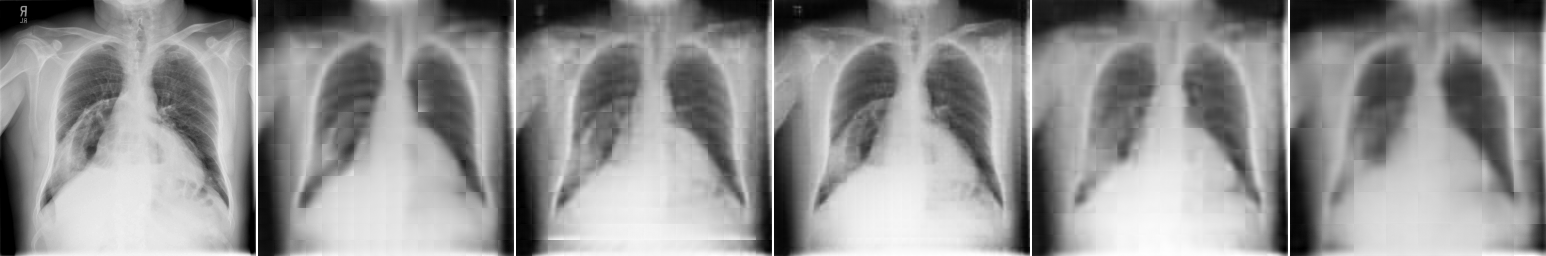

Image Patch Regeneration: Here, we vary the block size for image encoding and decoding to see how it will affect the image regeneration task. As shown in Fig. 5 and Table 4(b), block size renders the best image regeneration quality compared to other variants. Block size demonstrates higher classification accuracy with a moderate requirement of the computing resources (larger # patches per image will require larger GPU memories). As shown in Fig. 5, our proposed multi-scale image encoder and decoder can provide better regeneration results than a single-scale model. It generally suffers less from the blocking artifacts and is able to preserve more details, especially for pathological regions, as shown on the top two examples in Fig. 5.

The positional encoding used by existing works for image patch locations may not be sufficient to preserve the spatial information of images. This is because nearby image patches are often closely related, but direct patch predictions solely based on the features of each cell are not effective enough, which often lead to blocking artifacts (as shown in the result section later). It is one of the natural disadvantages of transformer-based methods for image processing compared to CNN-based ones. Here, we attempt to suppress this shortcoming within the general framework of transformer architectures. In Fig. 4, we illustrate a multi-scale image encoding and decoding process.